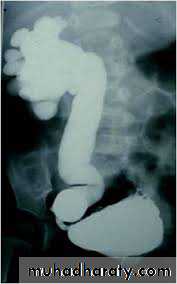

DIAGNOSIS

IVUDIAGNOSIS

CTTreatment